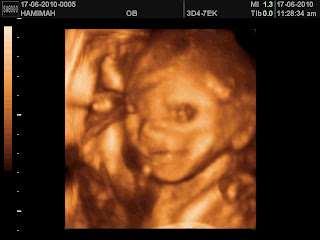

ni clip masa detailed scan hari tu

sweet smile for mommy :)

Hari ini usia kandungan saya memasuki minggu ke-23. Pagi tadi kami ke APSH buat detail scan - 3D scan. Lambat sampai sebab terlambat bangun.... huhu.... mujur prosesnya sekejap je. Baiknya baby hari ni... elok je position dia. Tak telangkup macam selalu... Umm bukan Doc Ariza... Lupa pulak nak tanya nama Doc tu... hehe...

Doc buat detail measurement; tak ingat sangat, tapi antaranya panjang kaki tangan, saiz otak, saiz jantung, saiz buah pinggang dll. All organ development completed. But, there's a concern... something related to kidney. The filteration system. Doc kata saiznya lebih besar tapi masih normal. Doc kata lagi, for XY selalunya saiz benda tu memang besar sikit. Aahh lega ceq dengaq.... But still need close monitoring katanya... uhhh